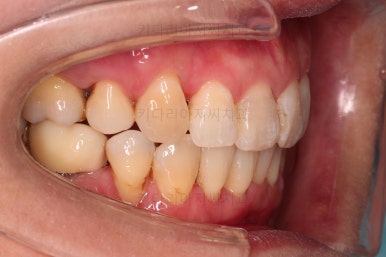

오늘 동래임플란트교정 키다리아저씨치과에서 소개해 드릴 환자분은 돌출입과 삐뚤어진 치열을 가지런하게 하고 싶었던 분이며 입 안에는 이미 임플란트가 되어있었고, 해당 임플란트 상부 보철물을 수정해야 했던 환자분입니다.

동래임플란트교정 초진 시 입안의 모습입니다.

치열이 전반적으로 삐뚤어져 있는 양상이고요.

아랫니가 윗니보다 더 많이 삐뚤어 있는데요.

얼굴 모습입니다.

치열이 삐뚤어 웃는 모습이 심미적으로 떨어지고요.

입술의 돌출감이 느껴집니다.